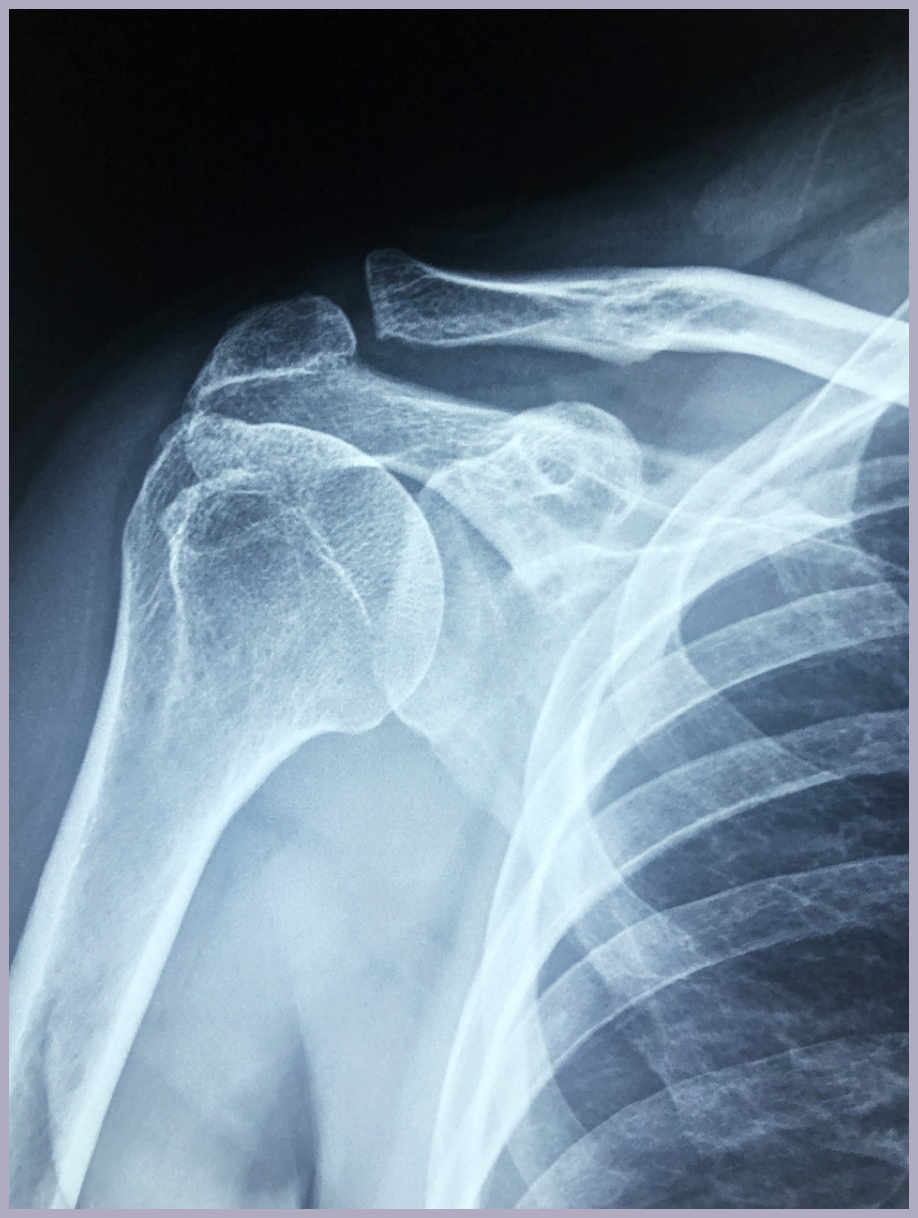

석회성건염의 진단은 주로 영상검사를 통해 이루어집니다. X-ray 검사에서 석회 침착물이 하얀 그림자로 관찰되며, 초음파 검사를 통해 더 자세한 위치와 크기를 확인할 수 있습니다. 필요한 경우 MRI 검사를 통해 주변 조직의 상태도 함께 평가합니다.